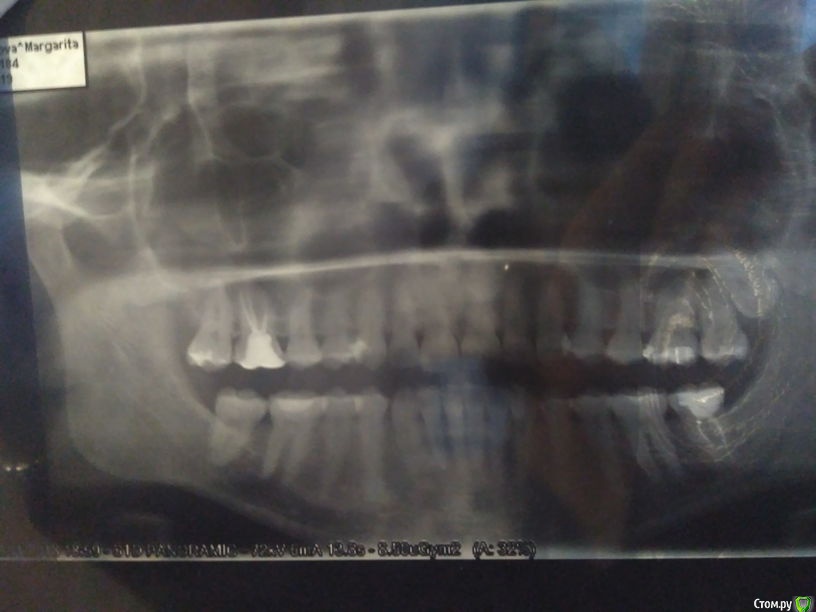

MargaritaM Опубликовано 15 января, 2018 Поделиться Опубликовано 15 января, 2018 Здравствуйте! Ранее я к Вам обращалась за советом - http://forum.stom.ru/topic/33953-verkhnie-retinirovannye-vosmerki-zuby-mudros/ Пол - женский, сейчас 29 лет конец 2016 годаВосьмерку удалили, всё прекрасно зажило. Шестерку перелечили - оказалось предыдущий доктор недоработал и как следует не заделала каналы, к сожалению, один из 3х каналов был испорчен предыдущим доктором и его не удалось пройти до конца. К сожалению, на этом злоключения не закончились. конец 2017 года - начало 2018 годаПрошел год и опять вернулись боли справа. В ноябре-декабре 2017 начала ныть 7ка, её обработали на тему чувствительности, вроде стало полегче. И вот 3 января стало болеть где-то в районе верхних правых 6ки и 7ки, реакции на накусывание или горячее/холодное нет, боли ночью усиливаются, из-за этого могла уснуть только к 3-5 утра.Пошла к доктору, зубы тестировали на холод, постукивание. 9го удалось найти кликику, где бы делали ЭОД. К тому моменту стало болеть и в области нижней 6ки. ЭОД показал, что выше нормы только в нижней правой шестерке, верхняя 7ка в норме, верхнюю 6ку не проверяли, т.к. она депульпирована. Сняли пломбу в нижней 6ке - дно белое, плотное, пульпа не обнажена, поставили временную пломбу. Около верхней шестерки изменений десны, вроде нет, цвет нормальный.Отправили к неврогологу, т.к. проблем с точки зрения зубов не нашли. К 11 января уже вся голова болит, справа болит сверху и снизу, постоянно, боль в течение дня не уходит, но к ночи сильнее. Невролог поставила диагноз: "невропатия тройничного нерва справа неуточненного генеза". И на приему невролога меня просят широко открыть рот и я тут понимаю, что мне немного больно это делать. Справа у уха болит косточка при нажатии. Если не нажимать - не болит. Болела ли она до этого - не знаю, т.к. не приходило в голову туда нажимать. Общее:- Хотела бы отметить, что жалобы на верхние шестерку-семерку-восьмерку были примерно с 2013-2014 года и имели (как сейчас понимаю) сезональный характер - жалобы в период с ноября по март, потом боль стихала. Сейчас впервые так нестерпимо больно, что уже не спишешь на чувствительность зубов.- Косточка справа у уха болела и ранее при нажиме (но изредка, непостоянно) лет с 15, но т.к. это редко, несильно и только при нажатии, то я не обращала на это внимания.- Муж говорит, что ночью зубами не скрежещу. На сегодня была у следующих докторов и версия событий такова: Невролог - невропатия тройничного нерва справа неуточненного генеза Отоларинголог - дисфункция височно-нижнечелюстного сустава справа Основной лечащий стоматолог-терапевт и коллега - дело не в зубах, нужен нейростоматолог Стоматолог-терапевт, к которому направили для независимого суждения: скорее всего, дело в верхней шестерке, недолечили канал и не нашли 4й канал. После немисила и карбамазепина стало намного легче. Днем немного побаливает, ночью может усилиться, но те страшные боли ушли. Динамика положительная - с каждым днем легче, после приема лекарст прошло 3.5 дня. На текущий момент не совсем понятно, к кому идти лечиться и в чем проблема (и есть ли она вообще).В приложении ОПТГ, снимок ВНПЧ, фото прикуса. Ссылка на комментарий

Bier Опубликовано 16 января, 2018 Поделиться Опубликовано 16 января, 2018 Врач смотрела КТ, не нашла... Могу предыдущее КТ выложить - поможете посмотреть? Сейчас где-то там неприятно, но боли из-за лекарст нет. Нет боли в конкретном зубе. Но вот внутренняя сторона челюсти, между щекой и зубами - болит при пульпации. Это похоже на недолеченный канал? КТ качать не буду, но мне даже видится переодонтит на этом зубе. 1 Ссылка на комментарий

Bier Опубликовано 16 января, 2018 Поделиться Опубликовано 16 января, 2018 16 - это верхний правый, 46 - нижний правый. в ЦНИИС не надо ходить. Надо к нормальным эндодонтистам зайти. В ЧЛХ тоже нечего вам делать.Благо в Москве нормальных врачей полно. да, несмотря на все ваши пункты в зубе может быть периодонтит. И судя по снимку скорее всего и есть. Ссылка на комментарий